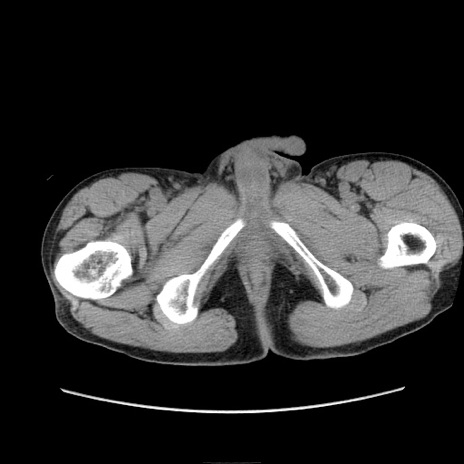

症例11(横断像)

【症例】 60歳代男性

【主訴】 下腹部痛

【現病歴】 本日夜中より下腹部痛の症状認め、受診。

【既往歴】 膀胱癌(膀胱全摘+尿管皮膚瘻術) 、胃癌術後

【身体所見】 BT 35.3℃、PR 58/min、BP 136/98mHg、腹部平坦、軟、腸蠕動音±、ストマ留置あり、左上腹部~正中部に圧痛あり、反跳痛なし。

【データ】WBC 5100、CRP0.01